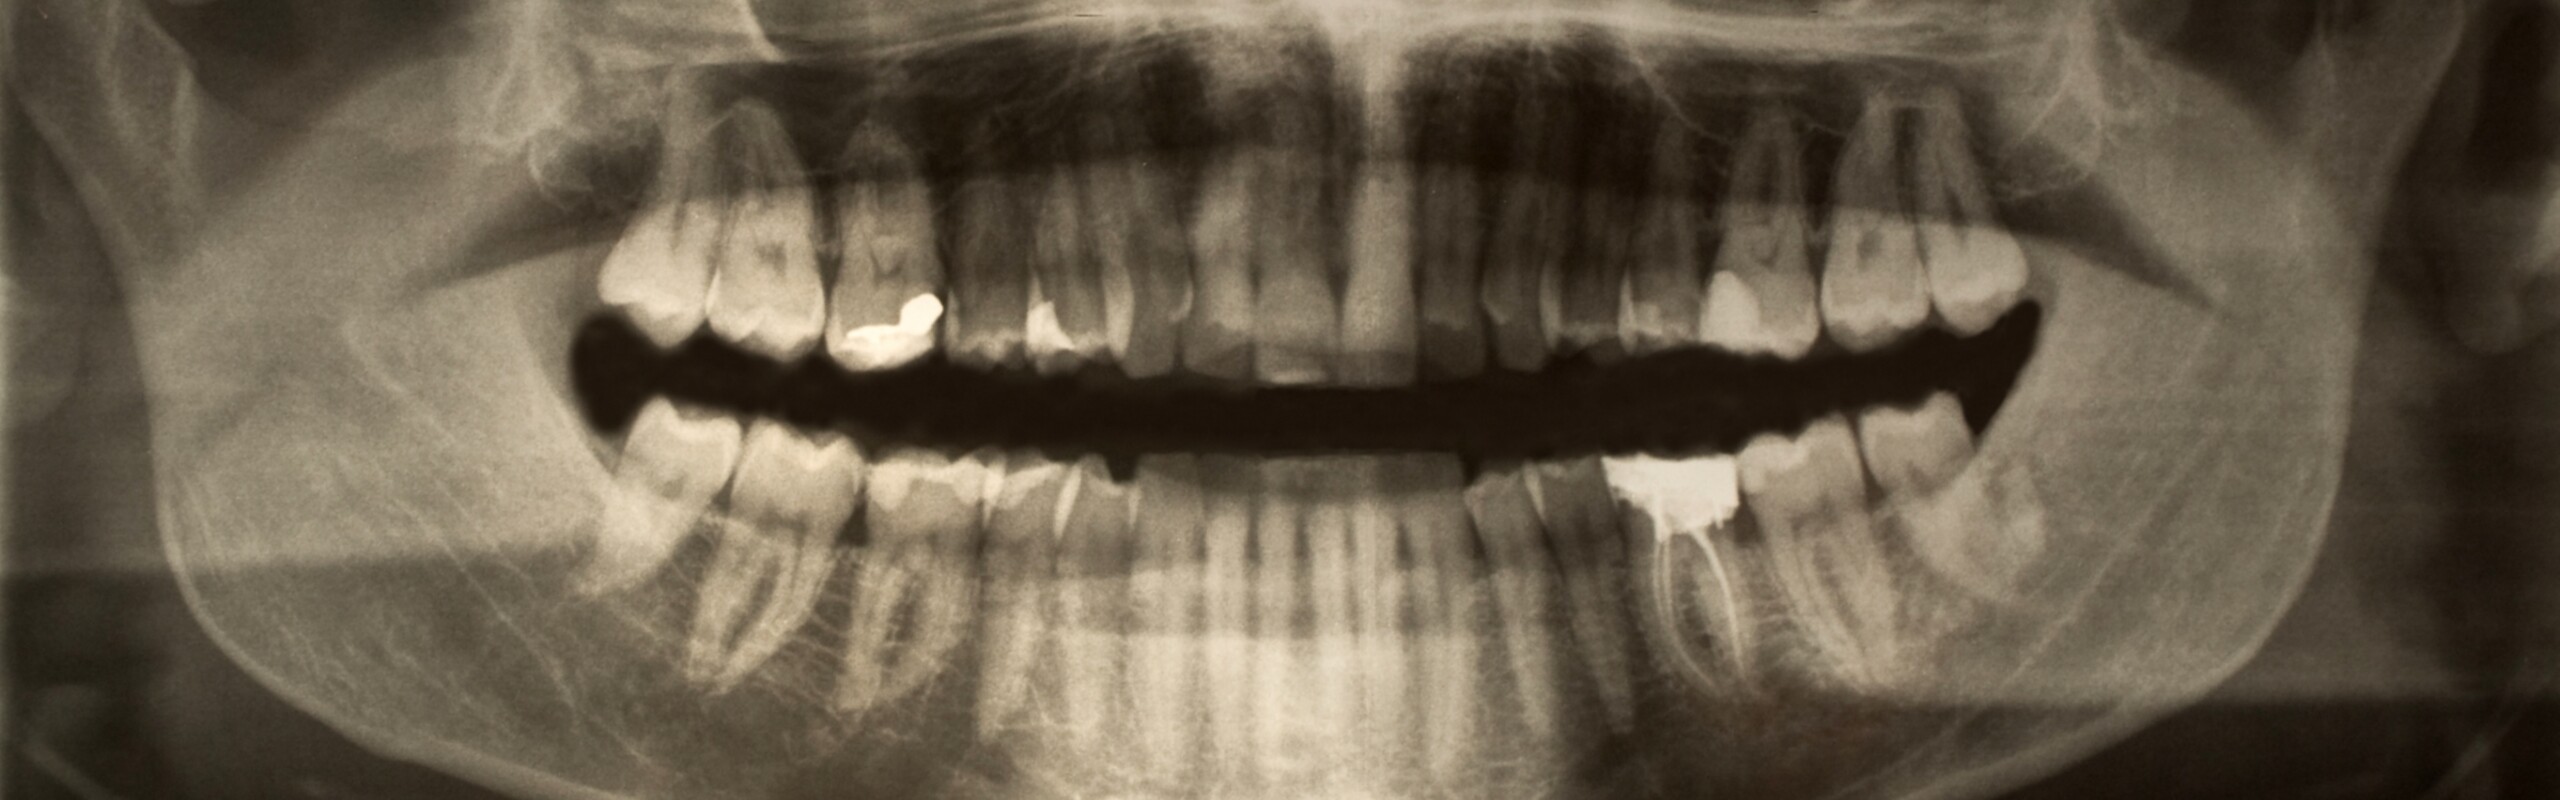

Research group Our group is studying the mechanisms of the bacterium A. actinomycetemcomitans in connection with periodontal diseases.

Periodontal diseases are among the most common chronic infections in the world, and rapid tooth loss in young individuals (<35 years) is strongly associated with infection by the Gram-negative bacterium Aggregatibacter actinomycetemcomitans. Its special properties make the role of this species most crucial in the initial stages of the tooth attachment loss process. Production of a leukotoxin in this bacterium is associated with high virulence, but we do not yet know why also low-leukotoxic isolates of the species can be highly virulent. A. actinomycetemcomitans is also reported to contribute to systemic diseases, such as cardiovascular disease, and rheumatoid arthritis, caused by hypercitrullination.